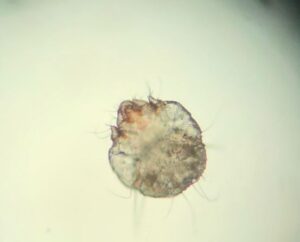

Culiacán, Sinaloa; a 11 de agosto de 2025.- La escabiosis o sarna en caninos, la cual la produce el ácaro Sarcoptes scabiei var canis, no es patógena para el ser humano, existiendo otras especies que son características de la sarna humana que es Sarcoptes scabiei var hominis.

José Mario Atondo Pacheco, especialista e investigador quien labora en el laboratorio de Parasitología de la Facultad de Medicina Veterinaria y Zootecnia de la Universidad Autónoma de Sinaloa (UAS), explicó que son las misma manifestaciones clínicas que en los animales, donde el contagio se da de dos formas; las directas, que son convivir con personas con Sarna, pareja sexuales, entre otras, mientras que la forma indirecta es el uso de sábanas en los hoteles, el compartir ropa usada que no está desinfectada, toallas, entre otras formas.

El especialista indicó que, entre los principales síntomas, está la comezón nocturna en humanos, el rascar en la noche en las zonas en el intermedio de los dedos, las axilas, los glúteos, la ingle, etcétera; en lo niños es rascarse la palma de las manos, los pies y la cabeza, por lo cual es de estar muy al pendiente de ellos ya que esta patología es altamente contagiosa.

Mencionó que el tratamiento en animales como en humanos es igual, una pastillita y baños, además en ambos casos se puede dar la irritación, que el ácaro del perro sí puede entrar al humano, pero con un baño de jabón y shampoo solo se mata, porque en el humano no es el huésped definitivo.